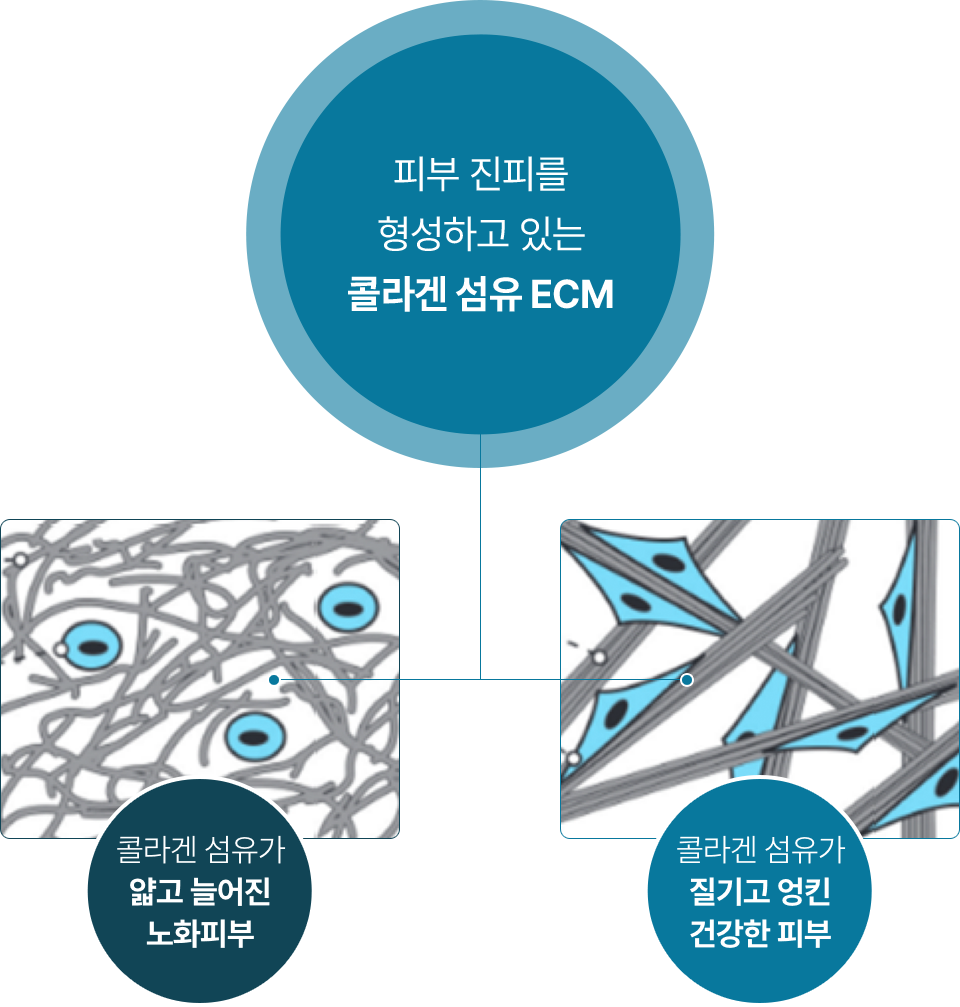

레디어스의 CaHA는 바이오 스티뮬레이터로

ECM 구성 성분 5가지를 만들어냅니다.

5가지 재생 성분은 약해진 피부 중심을 단단히 채워줍니다.

피부에 주입시켜 섬유아세포의 활성과 텐션을 회복하는 것은 바이오 스티뮬레이터인 레디어스의 가장 큰 특징입니다.

피부 탄력성, 두께감, 피부결 개선

조직회복, 콜라겐 1형의 구조적 지지

피부 탄력성, 피부 탄탐함

수분 보충, 피부 탄탄함

혈액 공급, 영양분 공급